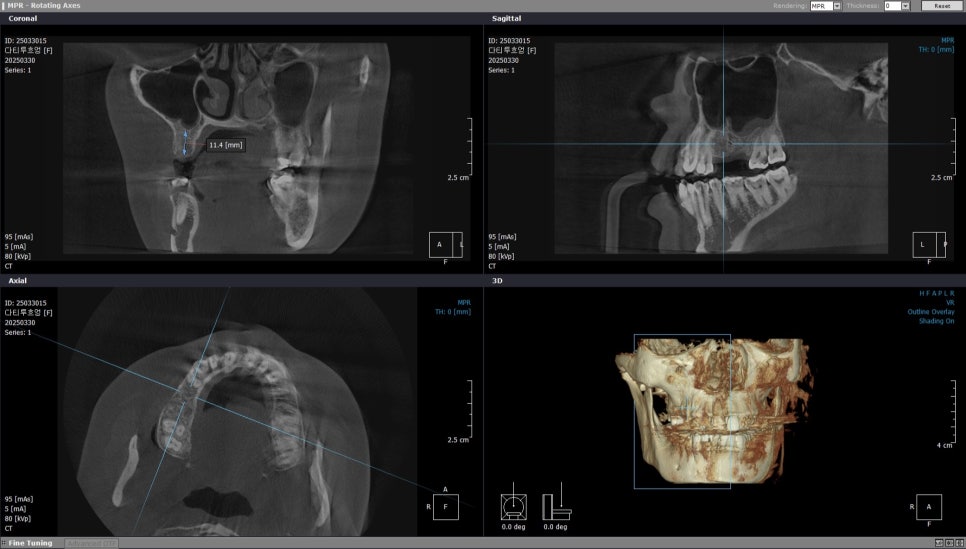

반면 바로 옆 두번째 작은 어금니 부위는

11.4mm의 충분한 골 높이가

확보가 되어있었고요.

오른쪽 위 두번째 작은 어금니는

골높이가 11.4mm로

임플란트 식립에 충분합니다.

오른쪽 위 두번째 작은어금니 부위